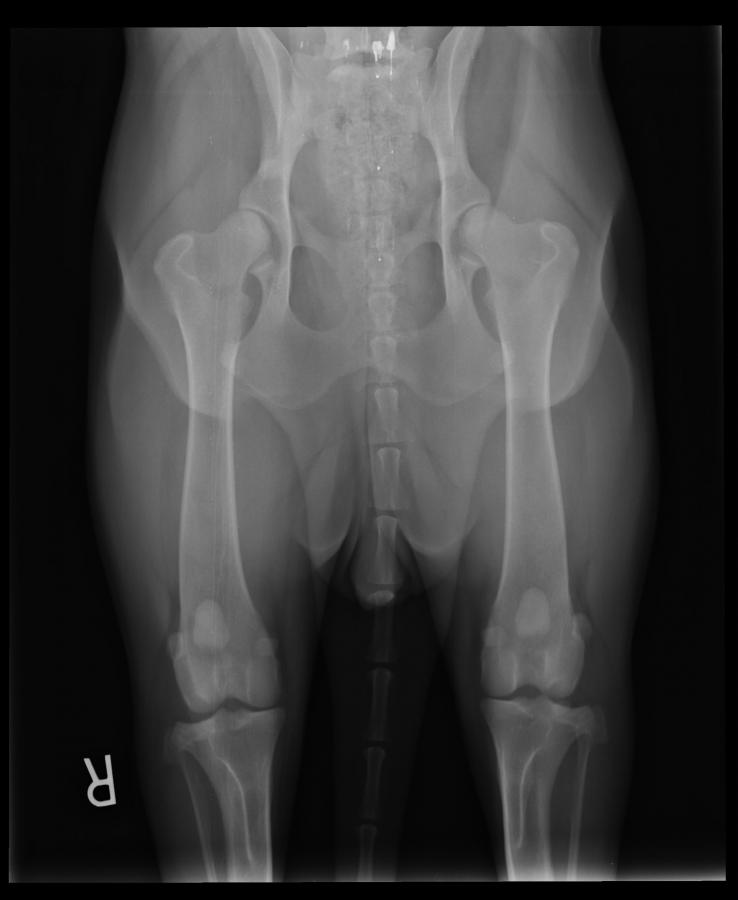

OFA good enough .. good to excellent and I can't see a reason why not excellent.

I can see OFA giving an Excellent or Good, more than likely a Good.

Not near deep enough sockets for OFA to say excellent.

Most OFA breeders and dedicated dog sellers rush their dog to the vet at 2 years and one day .... three year old results are very much more indicative than 2 year old results and 10 times better than the SV and their 12 months and 1 day results. Want to know what a dog's hips will be like at 8 years ??? X-ray at 8 years not at 12 months. The OFA and SV systems are about selling dogs and keeping the money flowing to the OFA and the SV. Neither OFA nor SV hip ratings can tell you what the offspring will be like and that is the big lie the SV and OFA are selling. As a three year old the dog in this post has excellent hips and could be used for breeding if she has the 100 other good traits that matter for breeding. Breeding or not breeding a dog based on hips is an idiotic scam based on the SV and OFA serving their own best interest.